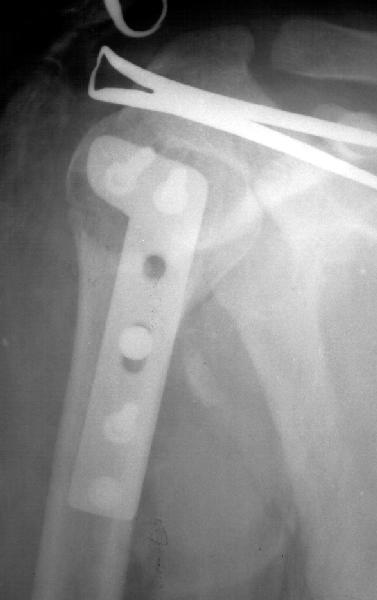

Мужчина 25 лет 16 августа 2002 г. в автоаварии получил перелом шейки плеча (снимок 1); 5 сентября в городской больнице выполнен остеосинтез пластинкой (снимок 2).К настоящему времени попал к нам на разработку ввиду выраженной контрактуры плечевого сустава. В течение последнего месяца беспокоят умеренные боли в области плечевого сустава, усиливающиеся при разработке, еще и торчит край пластинки. Нынешняя рентгенологическаякартина на снимках 3 и 4. Головка плеча уменьшается, сращение сомнительное.Кроме удаления пластинки, что еще на сегодня целесообразно сделать?Заранее спасибо.

1.Операция сделана через 3 недели после перелома, когда в месте перелома был уже фиброз - так это происходит нормально у молодого 25 лет человека и так мне видно на Х-фильме АР ( антеро-постериор). Решение оперировать в этот период абсолютно непонятно. Если решил сделать внутреннюю фиксацию, делай её до конца первой недели, а лучше в первые 3-4 дня. Решил лечить

консервативно - проводи это лечение до явных признаков сращения или ложного сустава. После 3 недель, для осуществления внут. фиксации уже необходимо открыть и зачистить до живой кости фрагменты перелома, т.е. проводить внутри-суставную операцию, очень проблематичную для судьбы плечевого сустава. По-моему, наложению пластины зачистка перелома не предшествовала.

2.Пластинка , на мой взгляд, худшее решение для перелома шейки плеча. Сама пластинка слишком груба и массивна, целая слесарня в очень чувствительной для повреждений суставе.